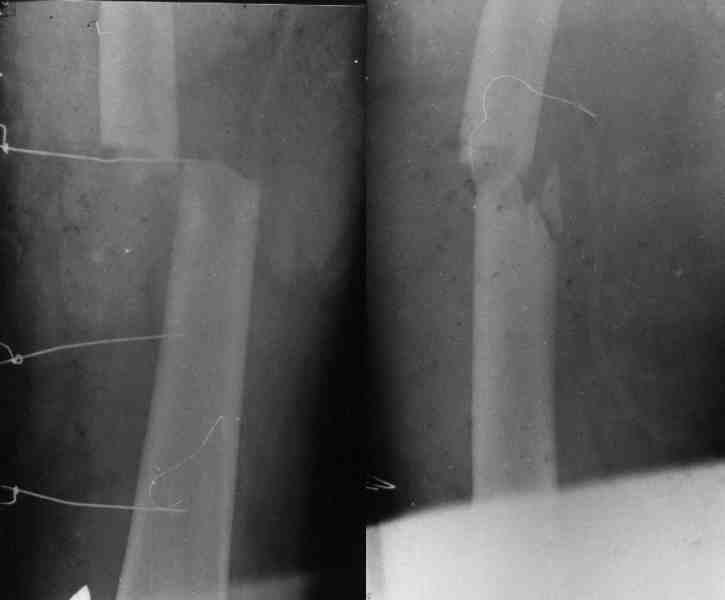

Re: Огнестрельный перелом плеча ( продолжение)

Вот еще информация, ознакамливайтесь pls/